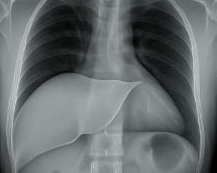

간수치 정상범위를 정확히 아는 것은 간 건강을 지키는 데 있어 가장 기본이 되는 정보입니다. 건강검진 결과에서 AST, ALT, GGT 수치가 높거나 낮게 나오면 막연한 불안감을 느끼게 되지만, 실상은 각 수치의 해석과 정상범위를 제대로 이해하는 것이 중요합니다. 오늘은 간수치 정상범위와 간수치란 무엇인지, 각 수치의 의미와 기준, 정상범위를 벗어났을 때의 원인과 대응 방법, 간수치 조절을 위한 생활 습관까지 체계적으로 정리했습니다. 이 글을 통해 간 건강에 대한 이해도를 높이고, 간수치 관리에 실질적인 도움을 받으시길 바랍니다.

이 수치들은 간세포 손상, 염증, 지방간, 음주, 바이러스 감염 등 간에 이상이 생겼을 때 변화하기 때문에 간수치 정상범위를 아는 것이 매우 중요합니다.간수치 정상범위, 왜 중요한가?

간은 침묵의 장기로 불립니다. 간에 문제가 생겨도 자각 증상이 거의 없기 때문입니다.

그러므로 건강검진을 통해 간수치 정상범위를 벗어났는지를 정기적으로 확인하는 것이 간질환 예방의 첫걸음입니다. 간수치 정상범위는 다음과 같습니다.- AST: 10~40 U/L